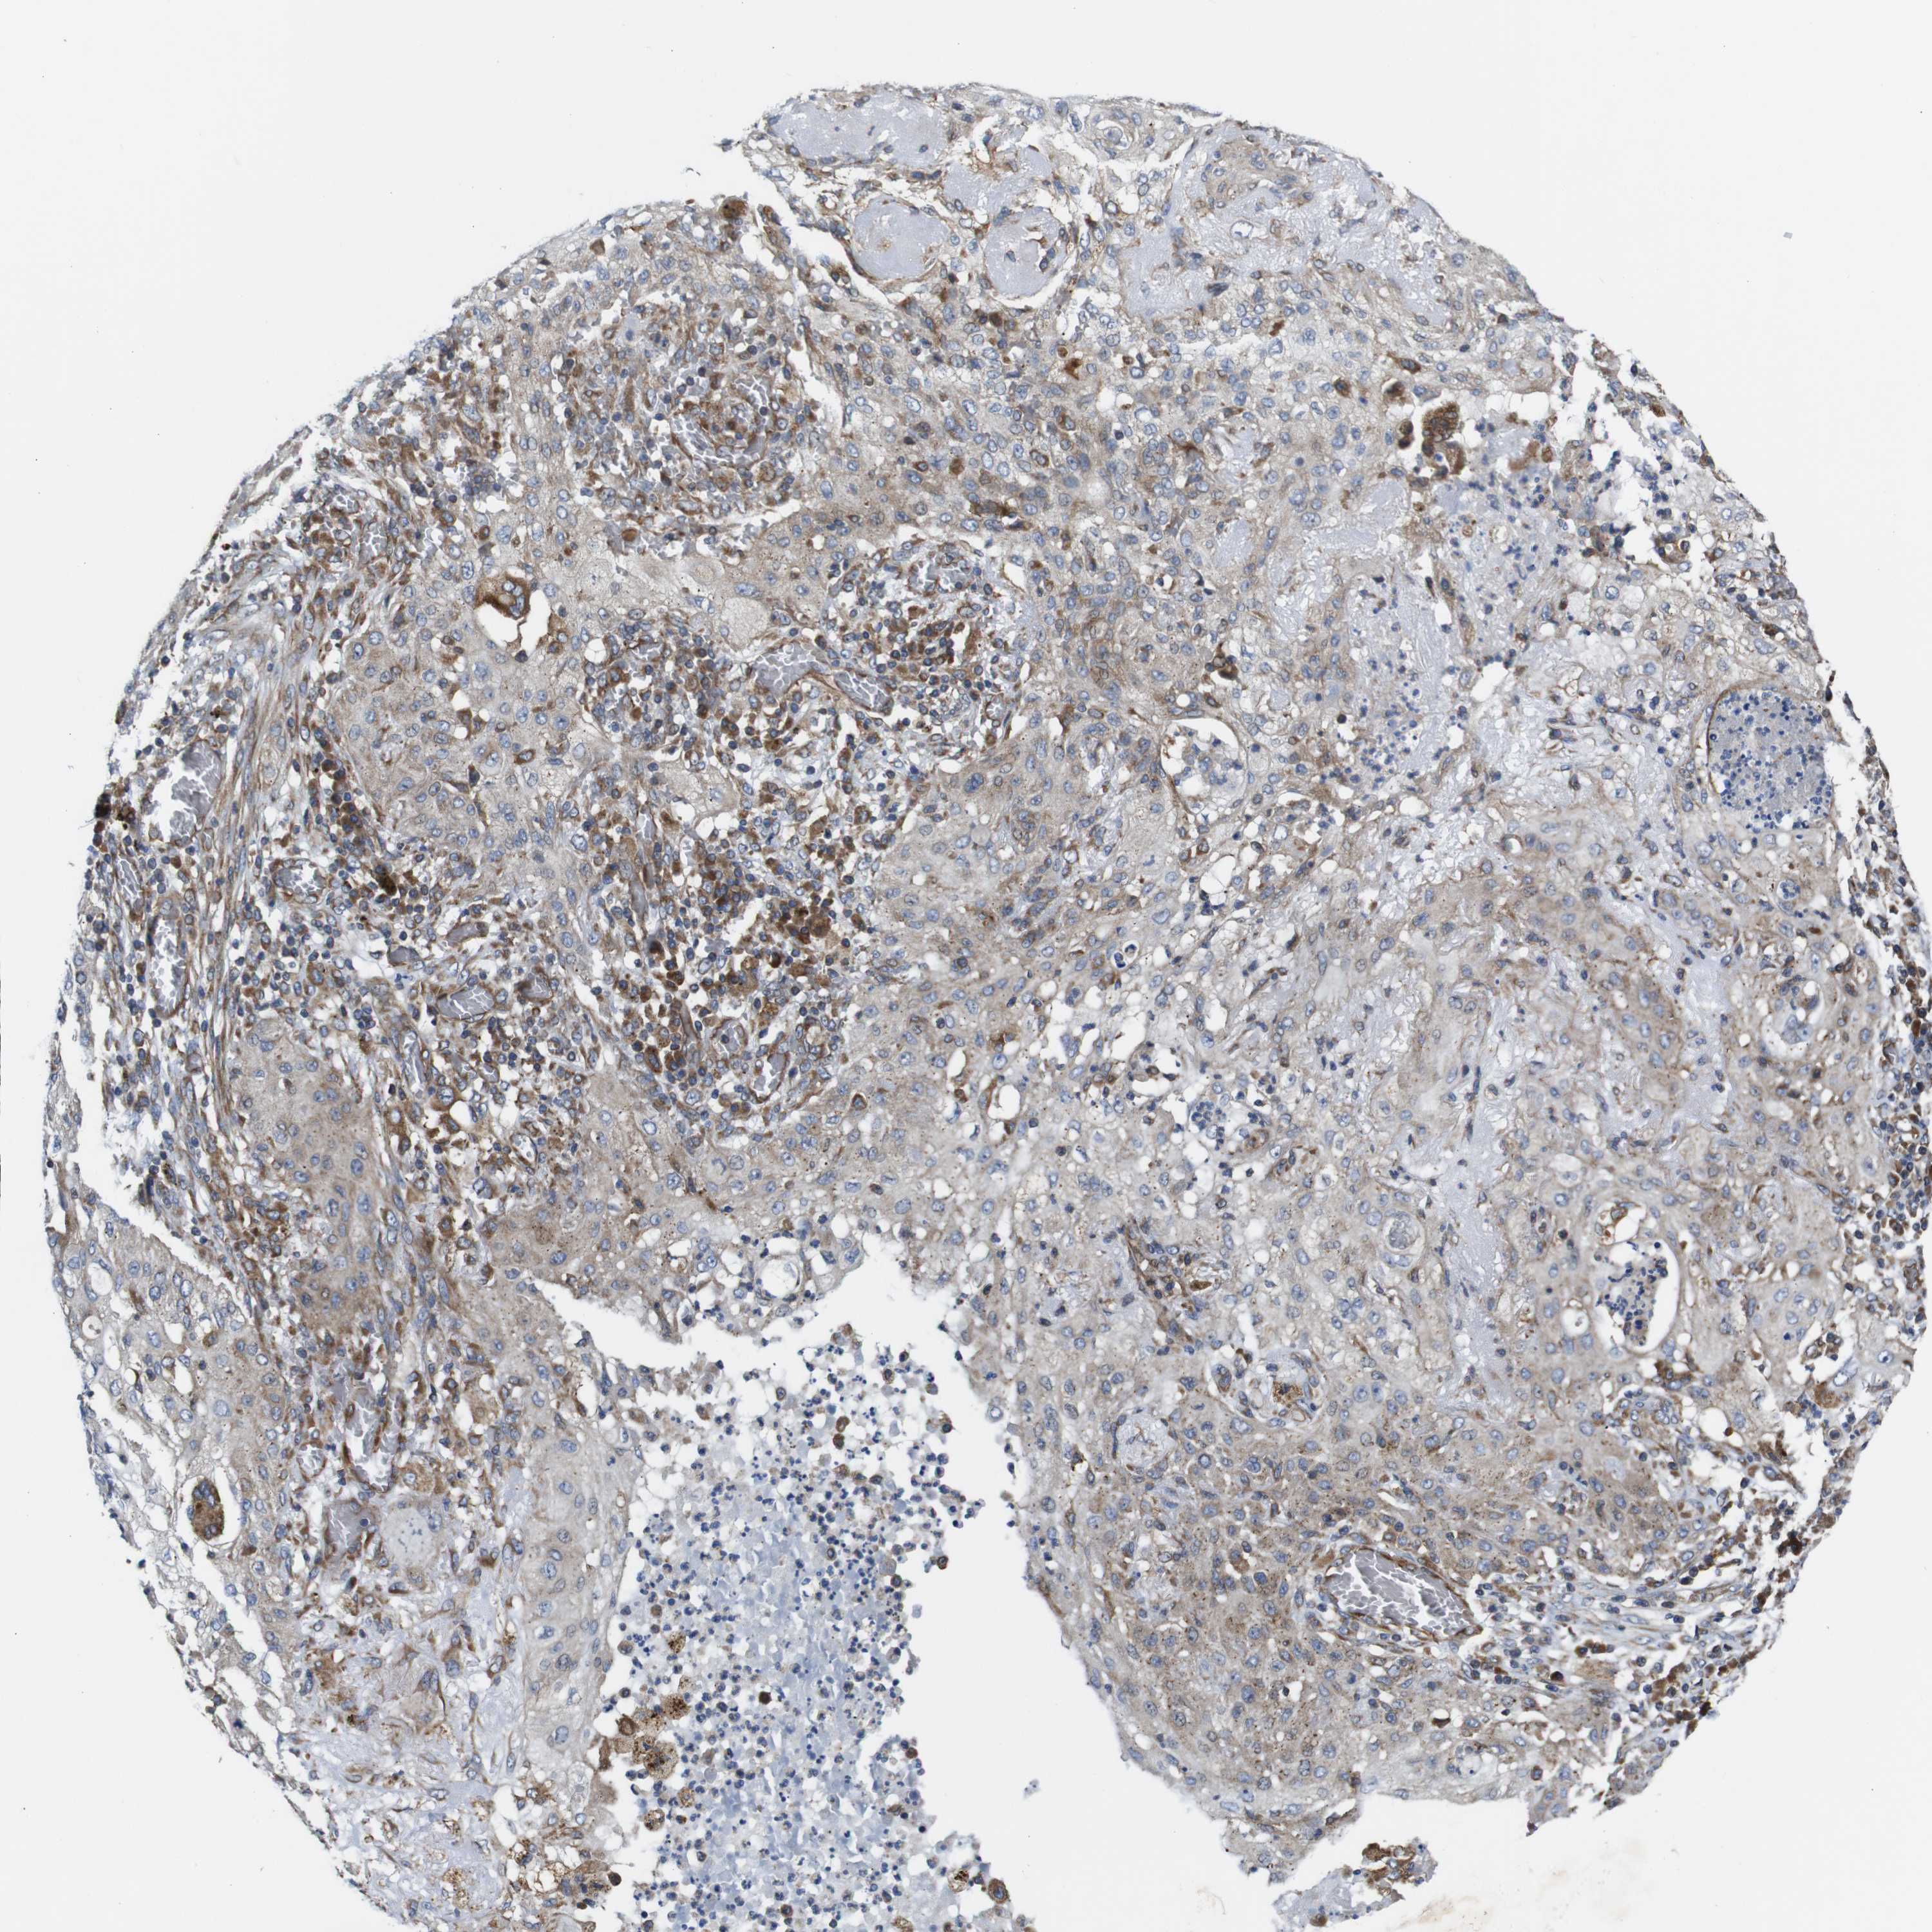

CANCER LUNG CANCER Show tissue menu

LUAD TCGA LUAD VALIDATION LUSC TCGA LUSC VALIDATION PROTEIN LUAD CPTAC PROTEIN LUSC CPTAC PROTEIN EXPRESSION